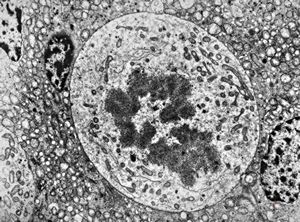

M,39y. | mitosis - chromophobic pituitary adenoma